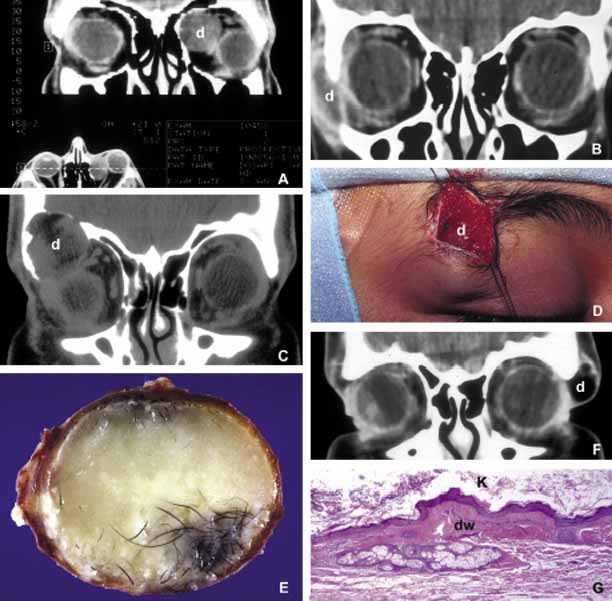

ANOPHTHALMOS/MICROPHTHALMOS When the globe is abnormally developed, microphthalmos, congenital cystic eye, and extremely rarely, anophthalmos occur. Microphthalmos usually occurs as a unilateral condition and in approximately 10% of cases it is associated with other craniofacial malformations including agenesis of the corpus callosum, polymicrogyria, and mid-line arachnoidal cysts. Microphthalmos may be seen as a part of several genetically determined neuronal migration disorders such as Walker-Warburg syndrome, Aicardi syndrome, and Fukuyama congential muscular dystrophy.9,10 In cases of microphthalmos and anophthalmos the orbit may be well formed but does not develop to a full adult volume. The mechanism by which the presence of the globe effects the growth of the orbit is not well understood. Microphthalmos may be associated with a colobomatous cyst as a result of the abnormal closure of the embryonic optic fissure leading to the prolapse of neuroectodermal tissues into the orbit (Fig. 1) This cystic structure may increase rapidly in size to overshadow the abnormal globe and may be confused with a neoplasm. When cystic lesions in the orbit are suspected imaging studies should be performed not only to look for other intracranial abnormalities but also to establish the possible connection of the cyst to the colobomatous globe versus to abnormally formed meninges.11 Macrophthalmos (buphthalmos) may also rarely develop as a congenital anomaly in patients with Sturge-Weber syndrome and rarely in neurofibromatosis type I. ORBITO-CRANIAL MALDEVELOPMENTS Cephalocele results from the extension of maldeveloped CNS tissues including meninges (meningocele), brain parenchyma (encephalocele), and the combination of the two (meningoencephalocele) into the orbital cavity.12,13 Intraorbital cephaloceles may develop anteriorly at the suture lines of orbital bones or posteriorly extending into the orbit from orbital fissures and the optic canal. Depending on the combination of these herniations they contain brain and/or meningeal tissues (Fig. 1). Aberrant fibroglial tissue has also been described in the orbit.14 Hamartoma is a tumor-like proliferation of tissues that normally exist at a given body location. The best examples of orbital hamartomas are the vascular hamartomatous lesions that are composed of vascular elements including capillary endothelial cells, distended or collapsed cavernous blood and lymph vessels, tortuous arterial and venous channels with or without anastomoses, etc. Other examples of hamartomatous orbital tumors include neurofibroma and lipomatous hamartoma.15 Choristoma, however, is a tumor-like proliferation of tissues that are not normally present at a given body location. The most commonly encountered example of orbital choristoma is a dermoid.16 Dermoids that present with many varieties result from the entrapment of epithelial structures at the site of closure of fetal fissures. Superficial dermoid cysts occur primarily subcutaneously anterior to orbital septum or within the anterior orbit. If the cyst wall is made of epidermis without dermal tissues, it is classified as an epidermoid cyst. These lesions are occasionally lined by conjunctival or pseudostratified respiratory epithelium.17 The superficial lesions must be distinguished from deep orbital dermoids that are usually rounded, encapsulated tumors filled with fatty materials, keratin, and dermal structures such as hair particles. Histopathologically the dermoid wall is lined by keratizing squamous epithelium with dermal appendices including hair follicles and sebaceous and eccrine glands.18 Most of the dermoids are well outlined by ultrasonography because of their anterior location thus making CT or MRI rarely necessary.19 If the dermoid is unusually large or located at the frontal zygomatic suture, CT is necessary to document the relationship of the lesion to the bone before surgical intervention. Rarely, dermoids at the fronto-zygomatic suture may develop dumbbell-shaped lesions partially within the orbit and partially extending into the temporal fossa.20,21 Unusually large superior orbital dermoids particularly those that leak and create granulomatous reaction within adjacent soft tissues may erode the bone and extend into the frontal sinus or the cranium (Fig. 2). ORBITAL TERATOMA Teratoma is a germ-cell tumor that contains tissues derived from endoderm, ectoderm, and mesoderm22 (Fig. 1). Therefore, these lesions may contain skin, bowel, lung, brain, thyroid, cartilage, and bone tissues. Most teratomas develop unilaterally and in girls. A majority of these congenital tumors are benign. Occasional reports have documented malignant transformation within orbitocranial teratomas.23 However, these benign tumors continue to grow after birth because of the collection of secretions from different tissues into the partially cystic spaces of the tumor. Some teratomas create massive proptosis and most can only be treated by exenteration. However, some of these lesions have recently been reported to be removed surgically with preservation of the globe and other vital orbital structures. TRAUMA Mechanical Injury Orbital injuries result from the absorption of kinetic energy that occurs whenever the orbital tissues contact an object moving at a different speed.25 The orbital rim is capable of absorbing a considerable amount of kinetic energy without being fractured. Yet, a variety of impact forces striking the orbit may result in fractures in different areas.26 The absorption of the kinetic energy by an orbital bone may lead to contusion and/or laceration of the skin and superficial soft tissues, local deformation of the adjacent structures, globe, orbital soft tissues and bones and increases pressure in the orbital cavity. A common end result of an orbital impact is the fracture of the floor and/or the medial wall (lamina papyracea)27 (Fig. 3). Fractures of other orbital bones occur less often. Foreign bodies may be introduced into the orbit at the time of injury and may cause secondary problems depending on the nature and the location of the foreign body.28 Some foreign bodies such as copper may cause tissue necrosis and degeneration (chalcosis), and others particularly organic matter, may carry organisms such as bacteria and fungi into the orbital tissues and cause secondary infections29 (Fig. 3). Once the fracture of an orbital bone occurs, it may produce sharp edges to lacerate adjacent soft tissue structures including the globe, optic nerve, other nerves, muscles, and vessels.30 Depending on the damage of the particular tissue, functional deficit results. Another issue to deal with in an injured orbit is the development of hematoma, hematic cyst, and cholesteotoma. Hemorrhage in the orbit may occur spontaneously without any physical exertion in healthy individuals. Although terminology is not very strict, hematoma usually refers to a localized collection of blood within orbital soft tissues that develops secondary to trauma. When the blood collection within the orbit becomes organized and surrounded by a thin pseudocapsule, it is known as a hematic cyst31 (Fig. 4). If the hemorrhage develops within an existing lymphatic or vascular tumor, these lesions are known as blood cysts or “chocolate” cysts.32 Hematic cyst consists of a localized collection of blood surrounded by a nonepithelium-lined thin fibrous capsule.33 These lesions usually develop within 1 to 2 weeks of orbital trauma but chronic cases may occur up to 20 years after orbital injury.34,35 They may reach to a size causing proptosis, extraocular motility disturbance, compression on the globe and optic nerve, that can easily be detected with ultrasonography, CT, or MRI. Hematic cysts may develop within the muscle cone or in the extraconal orbital locations.33–36 These cysts are lined by fibrovascular tissue at the periphery and contain degenerated erythrocytes, protein debris, and cholesterol crystals. In many instances the thin nonepithelial lining is adherent to the adjacent structures with fibrous tissue. Cholesteatoma is another cystic lesion that is confined within a “pseudowall” without an epithelial lining.37 Cholesteotomas are usually located in the superior lateral orbit within the lacrimal gland fossa. Imaging studies may show a cystic, semi-cystic, or a solid lesion within the diploe of the bone or within the orbital soft tissues, with or without erosion of the adjacent bone.38 Histopathologically the lesion is composed of cholesterol clefts, hemosiderin, and hematoidin granules, other blood breakdown products and fibrin surrounded by a mixed lymphohistiocytic infiltrate and multinucleated foreign body giant cells.39 On imaging studies these lesions appear as unilocular rounded masses with destruction of the adjacent frontal and zygomatic bones. Although bone involvement in general implies malignancy, the sclerosing character of the bony destruction in choleosteoma, which is best seen in bone window images, favors a benign lesion. Although bone destruction also makes one think along the lines of metastatic tumors, one should also consider benign lesions such as brown tumor, aneurysmal bone cyst, and ruptured dermoid. Multiple cuts of the frontal bone should be examined to rule out the possibility of intracranial extension. Osteomyelitis of the orbital bones evolving as a complication of paranasal sinusitis is another entity that should be considered in the differential diagnosis of cholesteotoma. In osteomyelitis the bone infection extends into the periosteal space and beyond. Precise delineation of the lesion can be performed with CT and MRI particularly in combination with bone SPECT, a sensitive technique used to detect osteomyelitis within cranial and orbital bones.40 Mucocele Although a commonly encountered space occupying lesion in the orbit, mucocele is technically not a neoplasm. It is a cystic cavity lined by pseudostratified respiratory epithelium prolapsing into the orbit from a paranasal sinus, most commonly the frontal followed by the ethmoidal sinus (Fig. 5). Primary mucoceles develop as a result of an inflammatory obstruction of the ostium of the paranasal sinuses. Secondary mucoceles, however, are most commonly seen after orbital trauma and surgery; they may also develop secondary to neoplasms of paranasal sinuses and nasopharynx. If there is a superimposed infection, the lesion is referred to as pyocele. The mucocele develops as a well delineated cystic structure originating from a paranasal sinus. Depending on the location, it may compress orbital structures including extraocular muscles, optic nerve, and the globe.41 Clinical presentation of the mucocele is usually with globe displacement and/or proptosis, extraocular motility deficiency, particularly in the direction of the sinus extension into the orbit, and other compressive symptoms.42 The crepitant or calcified hard wall of the mucocele may be palpated underneath the superior or medial orbital rim. Mucoceles in general, are rare in children, however, a unique variant, ethmoidal mucopyocele, is known to occur in the medial canthal area, with lateral displacement of the globe. On CT, mucoceles present as hypointense, expanding masses originating from the paranasal sinuses. Early in their development these lesions are small, mucous-containing cysts. Later they are characterized by crescent-shaped and thinned remodeling of the bony walls of the orbit and sinuses.43 On MRI, mucocele presents with different appearances depending on the amount of free water within its luminal contents. When the intraluminal mucous becomes inspissated, the signal intensity in both T1 and T2 images decrease, getting closer to normal air content of the sinus.44 Treatment of mucocele is surgical excision. Other injuries with toxic chemicals and radiation are known to damage orbital tissues.45–47 VASCULAR MALFORMATIONS Arteriovenous Fistula Orbital arteriovenous (AV) fistulas are established as a result of abnormal flow between the arteries and veins. These lesions can be divided into three basic types: carotid cavernous, dural and orbital AV fistulas. Carotid cavernous fistula is usually traumatic but may also develop secondary to a rupture of an aneurysm particularly in elderly atherosclerotic patients. These fistulas commonly develop between an intracavernous segment of internal carotid artery and cavernous sinus and shunt arterial blood into superior ophthalmic vein.48 Dural cavernous fistulas, however, develop between small meningeal branches of internal/external carotid artery and the cavernous sinus. These small vessels that have thin walls that may rupture spontaneously particularly in hypertensive individuals, secondary to minor trauma and maintain a low blood flow. Orbital AV fistulas usually develop secondary to traumatic rupture of the ethmoidal artery into the orbital venous system. This type of fistula maintains a low blood flow. Clinical findings of AV fistulas include rapidly developing proptosis, edema of the conjunctiva and eyelids, dilatation and tortuosity of the conjunctival and episcleral vessels, and secondary glaucoma. Most of these cases are diagnosed with imaging procedures including CT, MRI, angiography, color Doppler ultrasonography, and catheterized angiography.49 Current treatment of these lesions is embolization via catherization.50 Morphologic data are limited to autopsy material because most patients with AV fistulas do not undergo biopsy procedure. These lesions show irregular, malformed arteries and veins with abnormal elastic and muscular layers and secondary endothelial cell proliferation. Approximately half of the low shunt fistulas close spontaneously;51 therefore, it is best to follow-up some of these patients conservatively if they do not have severe symptoms. Orbital Varix Orbital varix is a rare vascular lesion with questionable histopathogenesis. The absence of valves in the orbital venous system and the weakening of venous wall may lead to pooling and stasis of blood resulting in distention of the venous channel with thrombosis. In gross appearance, the varix is a distended vein containing a canalized or uncanalized thrombus.52,53 Histopathologically varix consist of irregular vascular channels lined by endothelial cells. In chronic lesions, the blood vessel walls irregularly thicken with fibrosis and deposits of chronic inflammatory cells mixed with deposits of calcium and hemosiderin pigment are seen. Orbital varices are divided into primary and secondary types. The primary orbital varix is confined to the orbit as an isolated lesion without any connection to other A-V malformations. The secondary orbital varix, however, develops as an extension of an intracranial AV malformation that shunts blood to the orbital venous system causing the venous channels to distend secondarily.54 Management of orbital varix consists of total surgical excision when possible and/or endovascular embolization. | |||||||||||||||||||||||||||||||||||||||